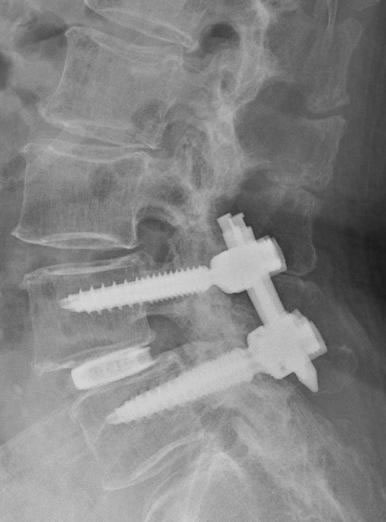

そのような患者さんには椎弓切除のみでは症状の改善が期待できないため、内視鏡下椎体間固定を行います。

内視鏡にて、移植骨、およびケージの挿入経路を作成します。

内視鏡腰椎椎体間固定術レントゲンと術後創部